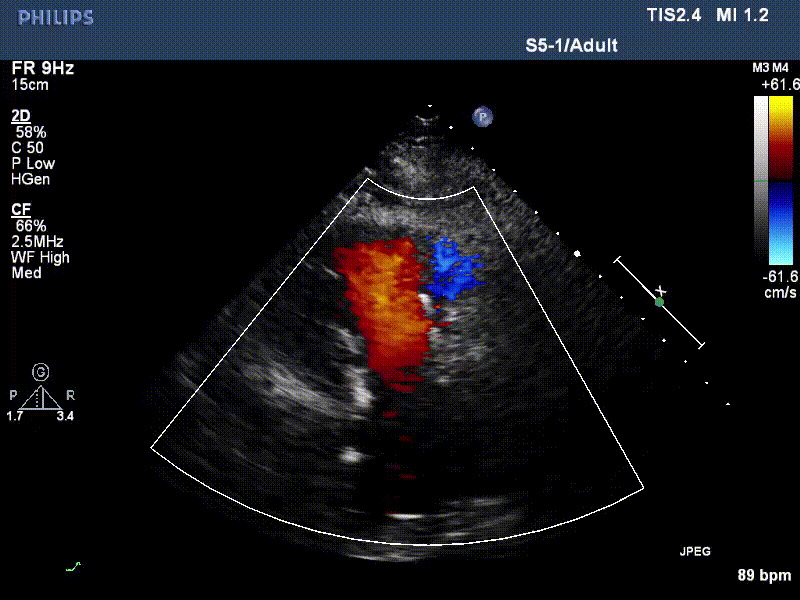

流并分別伴有房顫和房撲,高外科手術風險。術前超聲提示,兩例患者下腔靜脈寬度分別為13mm和29mm,右房內(nèi)徑(上下徑和左右徑)分別為52×41mm和53×43mm,彩色多普勒顯示極重度三尖瓣反流,VCW分別為14×15mm和10mm。

1年前,兩例患者因難治性雙下肢水腫輾轉多家醫(yī)院尋求救治,考慮到兩例患者高齡、基礎疾病多、STS評分高,不適合傳統(tǒng)外科開胸手術,葛均波院士及其團隊周達新教授、潘文志教授、張源博士、陳莎莎博士、陳丹丹博士聯(lián)合心外科王春生、魏來主任,麻醉科繆長虹、郭克芳主任以及心超室的潘翠珍教授、李偉教授共同討論決定,采用我國創(chuàng)新器械LuX-Valve Plus經(jīng)血管三尖瓣置換系統(tǒng)為患者進行手術。相較于第一代產(chǎn)品LuX-Valve,LuX-Valve Plus經(jīng)血管三尖瓣置換系統(tǒng)對輸送系統(tǒng)進行了全面升級,實現(xiàn)了經(jīng)頸靜脈入路的方式,進一步減小了手術風險和對患者的創(chuàng)傷。目前隨訪1年心超結果顯示,三尖瓣極重度反流消失,人工三尖瓣瓣膜穩(wěn)定牢固,瓣葉活動度良好,右心室及下腔靜脈明顯縮小,心輸出量增加。兩位老人手術后沒有出現(xiàn)過胸悶氣促的癥狀,下肢水腫緩解,活動耐力提升,生活質量也大為提高。

圖2 患者植入LuX-Valve Plus后,1年隨訪心超提示無三尖瓣反流